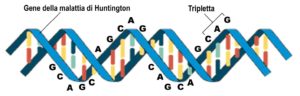

La malattia di Huntington è più comune di quanto pensiamo?

Più persone potrebbero avere il potenziale di sviluppare la malattia di Huntington, secondo uno studio pubblicato il 22 Giugno 2016…